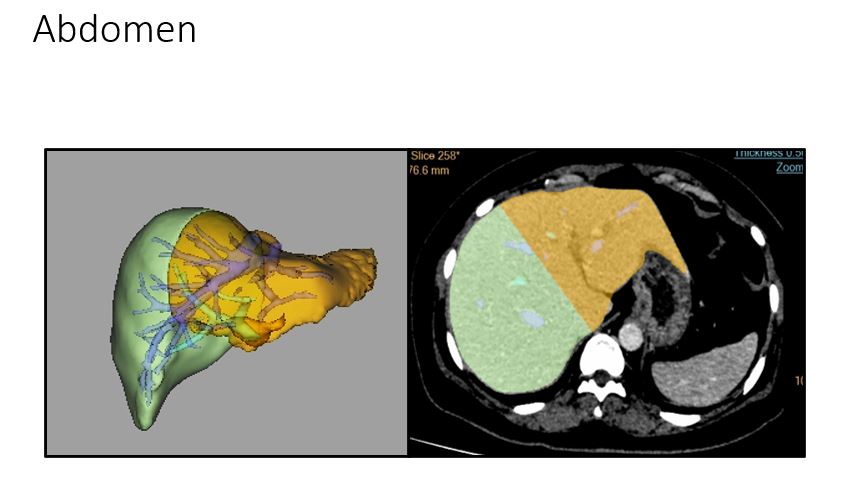

Abdominal Imaging & Interventions:

Diagnostic:

- USG: routine abdominal examinations

- USG contrast examinations – for mass characterisation, leaks

Adult and paediatric imaging:

- CT enterography, enteroclysis, CT colonography

- CT angiography – for vascular diseases, peripheral

- All contrast enhanced studies – intravenous, sinogram, cystogram, cavitogram

- Multi-organ transplant workup and follow up services, Volumetry

MRI – dynamic pelvic floor evaluation: